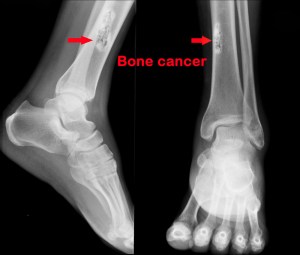

People with LFS, as the syndrome is often called, are especially susceptible to osteosarcoma, a form of bone cancer that most often affects children. Despite numerous research advances, survival rates for this type of cancer have not improved in over 40 years.